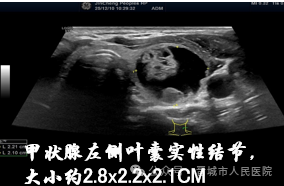

今年常规体检中,张先生的超声报告显示甲状腺左侧叶有囊实性结节,大小约2.8x2.2x2.1cm。看着报告上的 “结节” 二字,他满心纠结:“这结节是良性还是恶性?开刀的话脖子会留疤,还得住院好几天;不治又怕结节越长越大,压迫气管可怎么办?”

结合张先生的结节性质(良性囊实性)、大小及身体状况,晋城市人民医院介入科王丽云主任为他量身定制了热消融术方案。